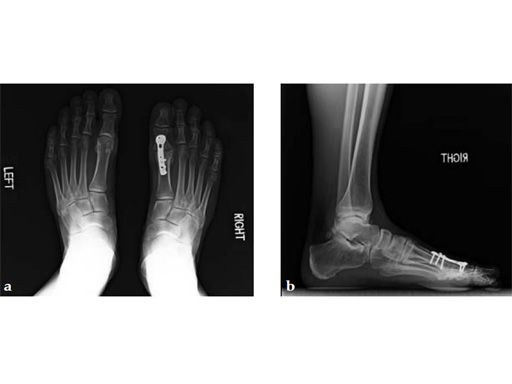

Case 2: First MTP fusion plate

A 38-year-old man presented for opinion after two attempts to fuse the big toe MTP joint. The AP view is significant for luscency at the joint line. The lateral view is notable for loosening of the hardware and malposition because of the dorsiflexion built in to the precontoured implant. Revision was planned using a 0 variable angle locking/compression hallux MTP plate.

Case provided by Michael Castro, Scottsdale, Arizona

At 10 weeks postoperatively (see Fig. 2ab) the patient had no pain with weight bearing. The lateral view demonstrates improved position of the toe using a 0angle plate.